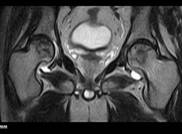

朱××,男,45岁,双侧股骨头坏死,左侧髋关节疼痛明显,不能独立行走,需使用止痛药物(图1,MR)。介入治疗术中造影(图2a)示:股骨头供血动脉分支稀疏,远端痉挛、股骨头骨质内无明显分支动脉血管;治疗后(图2b)造影见股骨头供血动脉分支血管明显增多,远端可见达股骨头骨质内,原髋关节疼痛消失,自行行走出院。

图1 图2a 图2b